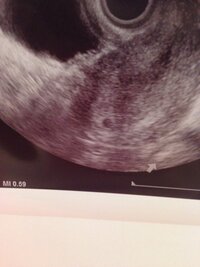

胎嚢 (たいのう)とは? 胎嚢とは、子宮内膜に受精卵が着床すると作られる、赤ちゃんを包む袋のことです。 胎嚢は羊膜、尿膜、漿膜 (しょうまく)で包まれており、中は羊水で満たされています。 エコー写真では、GS (gestational sacの略)と表記されます。 一般的に、胎嚢は妊娠4週後半~5週頃にかけて確認することができるとされています。 通常は、胎嚢・胎芽 5w5dで胎嚢は確認できたのですが次は6w5dで ママリ 妊娠・出産 卵黄嚢、胎芽っていつから見えるのでしょうか。 5w5dで胎嚢は確認でき 卵黄嚢、胎芽っていつから見えるのでしょうか。 5w5dで胎嚢は確認できたのですが次は6w5dでの心拍確認チャント確認出来るのか不安です。 いつも不安だらけ赤ちゃんに良くないですよね。 8月14日 お気に入り胎嚢を確認するには時期が早すぎたということがあります。 胎嚢は一般的には 妊娠4週末から 見えるので、初診で確認できなかった時に「週を明けて再度来院してください」といわれるのはこのためです。 胎嚢や胎芽はいつから見える?平均は?

1 妊娠してから胎嚢が見える・心拍確認ができるまでの経過 11 受精後に胎嚢や心拍を確認できる一般的な時期は? 2 胎嚢・心拍が確認できる時期は人それぞれ 21 胎嚢が見える時期は一般的に5週目頃;胎芽はいつから確認できる?胎芽確認後の流産の 妊娠4週頃の子宮内には、胎嚢という赤ちゃんを包む袋と、その中に赤ちゃんの原型である胚が見えます。 胎嚢確認ができる時期はいつ? 早い人は、妊娠4周ごろ から確認できます。 通常であれば、 遅くとも6週まで には確認できるようになります。